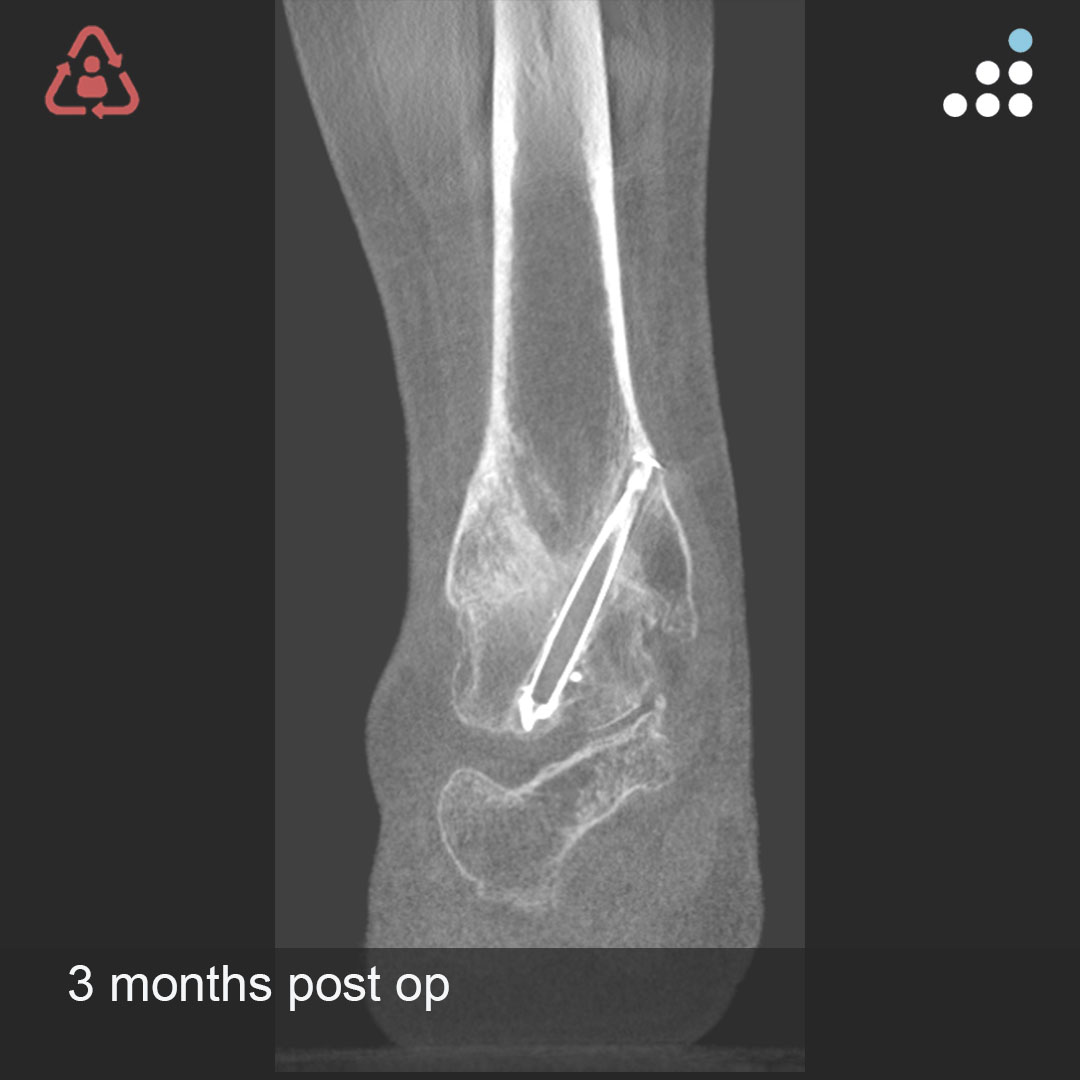

Here are intra-op & post-op images of yesterday's case by Dr. Jan Szatkowski(@orthotraumamd) & @IU_Health.

ANKLE PAIN 9 MONTHS S/P OPEN ANKLE FRACTURE-DISLOCATION IN 33M

Do you agree with the treatment? Why or why not?

Comment & keep the great conversation going!

#orthotwitter